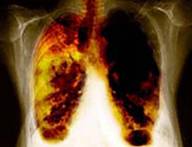

Good news! Good news for those who want go in for TB tests but are apprehensive and suspicious about the currently used lengthy method of testing. The World Health Organization and a number of global health partners have teamed up and announced the $26.1 million initiative wherein they will begin converting the molecular-based testing laboratories in more than two-dozen of the poorest nations to genetics testing (for tuberculosis) laboratories. "Line probe assay," a kind of DNA test will be used by the clinicians for diagnosing the deadly TB. The new test will be useful in determining a patient's TB status also. This test will give the results within a day whether someone is infected with a strain of tuberculosis that is resistant to the more common antibiotic drugs so more aggressive therapy needs to be started. TB tests which are employed currently involve a culture that can take weeks to months to process, at a time when the number of cases of multi-drug resistant tuberculosis, or MDR-TB, is growing. TB is difficult to diagnose because many of its symptoms, such as fever, fatigue, and loss of appetite. "Line probe assay" can provide a much quicker result than existing testing methods, for which results take up to several weeks. FIND is a Geneva-based organization that developed the rapid TB test for clinical use and is now helping countries to prepare to use the new laboratory technology. Rick O'Brien is head of project evaluation for FIND. "We see this test as having the potential to revolutionize the diagnosis of MDR-TB and make a significant contribution to controlling this expanding and critical epidemic," he said. With this initiative, field trials of the DNA test in South Africa were followed which showed that the new test performed as well or better than the worn-out method of diagnosing TB with a microscope. According to Officials, each DNA test costs approximately five dollars, and it takes about one week to train a laboratory technician. A pilot project was conducted in Lesotho, which now has a state-of-the-art laboratory system ,officials say. "We say today that Lesotho, one of the poorest countries on the Earth, has a laboratory system that is equivalent to those that you find in the best countries in Europe or North America. So it's something that requires a focused effort but is feasible," said Mario Raviglione, director of Stop TB at the WHO in Geneva. Ethiopia is expected to be ready to employ the new DNA TB tests by the end of the year. Over the next three years the technology will be phased in 14 more countries. |